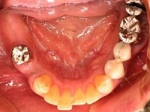

上部装着後のレントゲン像上部装着後のレントゲン像上部装着後のレントゲン像 術前口腔内写真術前口腔内写真術前口腔内写真 術後口腔内写真術後口腔内写真術後口腔内写真、食事がおいしくなったと非常に満足されている。